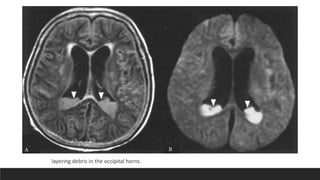

CT

• usually unhelpful in diagnosing infection.

• Ependymal enhancement when it occurs is

is diagnostic of ventriculitis.

• CT may demonstrate shunt malfunction

layering debris in the occipital horns.